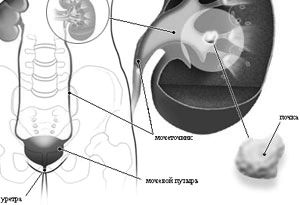

Освіта сечокислих каменів в нирках - це найчастіше ускладнення уратурія, і саме воно вимагає, лікування. Лікування мочекислого діатезу направлено на запобігання утворенню каменів, але при вже наявних каменях вона безсила. У цьому випадку, щоб полегшити відходження каменів, призначають їх апаратне дроблення - високочастотним ультразвуком, лазером або механічним способом. Кожен метод має свої переваги і недоліки і застосовується в різних ситуаціях.

Мета дроблення каменів - зменшити їх розмір, завдяки чому вони будуть менше травмувати сечовивідні шляхи, спускаючись по ним. Це знижує не тільки больові відчуття пацієнта, а й ризик кровотечі і запальних захворювань сечоводу, сечового міхура і уретри (особливо у чоловіків).

У важких випадках, якщо камені в нирках мають великі розміри і дроблення каменів неможливо, призначається операція з їх видалення - ендоскопічна, якщо вона можлива, або лапаротоміческім. Показання до неї - великий розмір каменів, множинні камені при наявності протипоказань до літотрипсії, важкий стан пацієнта, викликане ниркової колькою.